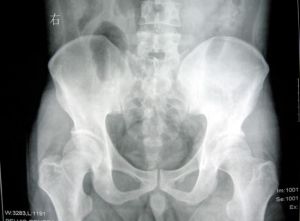

骨盆癌影像學表現骨盆環是由骶骨和兩側的髖骨組成,每側髖骨由髂骨、坐骨和恥骨構成。骨盆被肌肉所覆蓋,這些肌肉起到了限制腫瘤直接侵犯鄰近血管神經束的作用。例如,當髂骨腫瘤突破骨皮質向內或向外生長時,總是有肌肉覆蓋在腫瘤表面,外側有臀肌包裹,內側有髂肌和腰肌,這些肌肉均有明顯的筋膜覆蓋(特別是起於髂嵴的髂肌),是防止腫瘤向腹部及盆腔擴散的良好屏障。

發生於恥骨的腫瘤鄰近經過恥骨支前面的股神經血管束,但這些血管神經束有較厚的筋膜,使之不易被腫瘤直接侵犯。坐骨神經在坐骨大切跡處與骨盆最接近,當腫瘤蔓延至坐骨切跡時可以緊鄰坐骨神經。發生於恥骨聯合部位的骨盆腫瘤相對較少,對此部位的腫瘤進行手術時應注意保護膀胱和尿道。